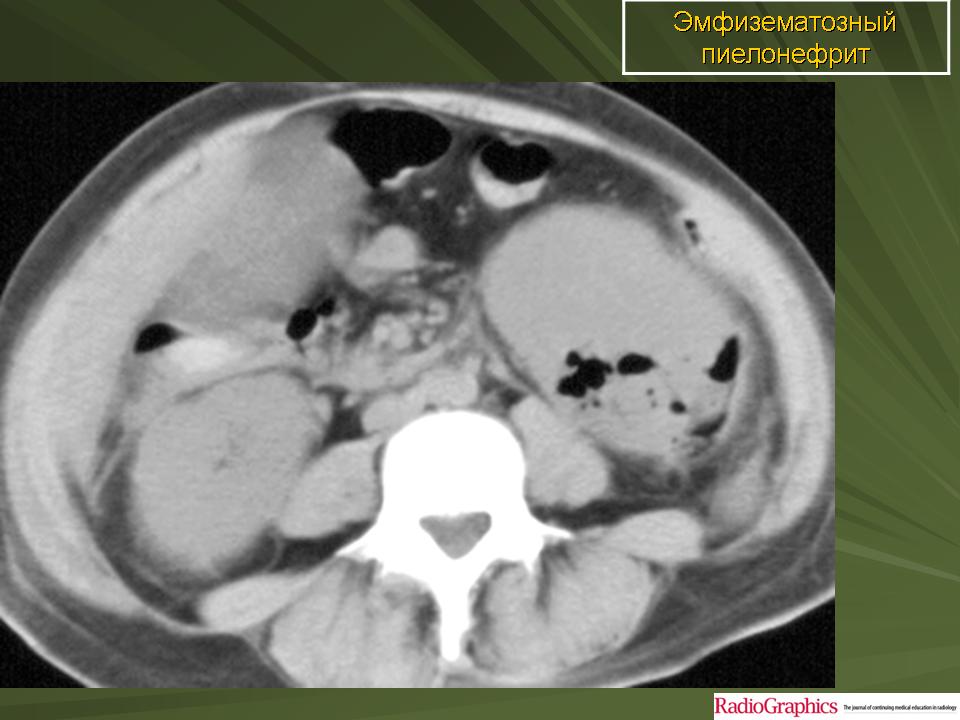

Эмфизематозный пиелонефрит

ID: 17283 Emphysematous pyelonephritis Dr Maulik S Patel - 1 Apr 2012 Emphysematous pyelonephritis

ID: 24370 Emphysematous pyelonephritis Dr Ian Bickle - 10 Aug 2013 This is a case of emphysematous pyelonephritis. This constitutes only a...

ID: 23334 Emphysematous pyelonephritis Dr MT Niknejad - 7 Jun 2013 The CT findings in a 76 Y/O diabetic patient with fever , flank pain and...